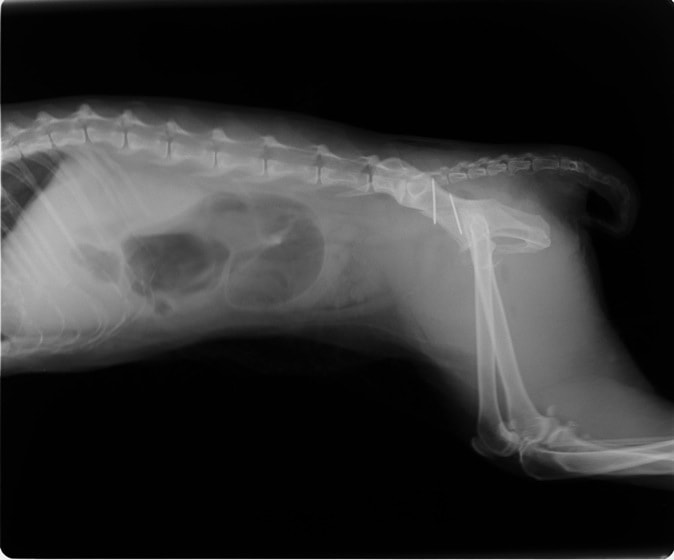

症例:交通事故による椎体脱臼

柴犬:9歳、避妊雌

交通事故直後、胸腰部に激しい疼痛、両後肢に完全麻痺を認め、シェフシェリントン徴候を呈していました。レントゲン検査において、第11-12胸椎間の脱臼が認められました。

脊髄の減圧、脊柱管の再構築・安定化を目的に、片側椎弓切除術およびMatrixMANDIBLE Plateによる椎体固定を実施しました。

隣接椎体を架橋するようにプレートを設置しました。

術後レントゲン写真